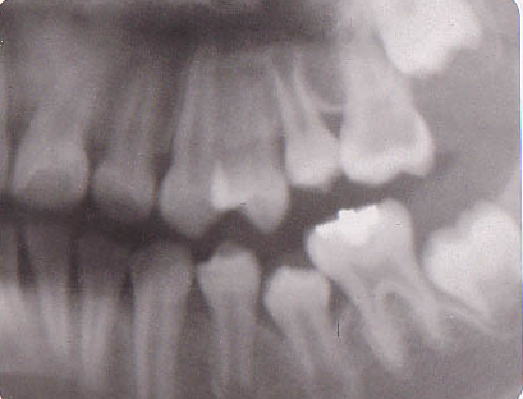

| 乳歯は、それぞれの年齢で重要な役割を果たしています。 そして、ある時期が来ると下から萌出してくる永久歯と交換します。 もし、交換すべき時期より虫歯が原因で早く喪失してしまったらどうなるでしょうか。 例えば、下の写真(図1)を見て下さい。永久歯が歯と歯との間にはさまれて出てこれなくなっています。 また、図の2のように、乳歯は、下から萌出してくる永久歯の場所を確保している役割を果たしています。 どうせ永久歯と交換するから虫歯になっても関係ないと考えるのは大きな間違いです。 乳臼歯は、10歳頃に永久歯と交換します。もし、虫歯でもっと早い時期に喪失すればほとんどの場合下の図1の写真のような状況を引き起こします。 そして大人になっても同じ状況が続きます。周囲に食べかすが溜まりやすく虫歯や歯周病になり、不正な萌出をした歯やその周囲の歯が失われていく可能性が高くなります。ブリッジや入れ歯が必要になります。ブリッジならその周囲の歯を削ることになり、削った歯は、削らない歯より寿命が短くなります。入れ歯も同様です。また、治療をしないでそのままにしておくと図の3のように歯が移動してかみ合わせが悪くなり、歯列不正や顎関節症など様々な問題を引き起こします。そういう悪循環で歯がどんどん失われていくことになります。図4 御理解いただけたでしょうか? たかが、乳歯と思わないで下さい。 |